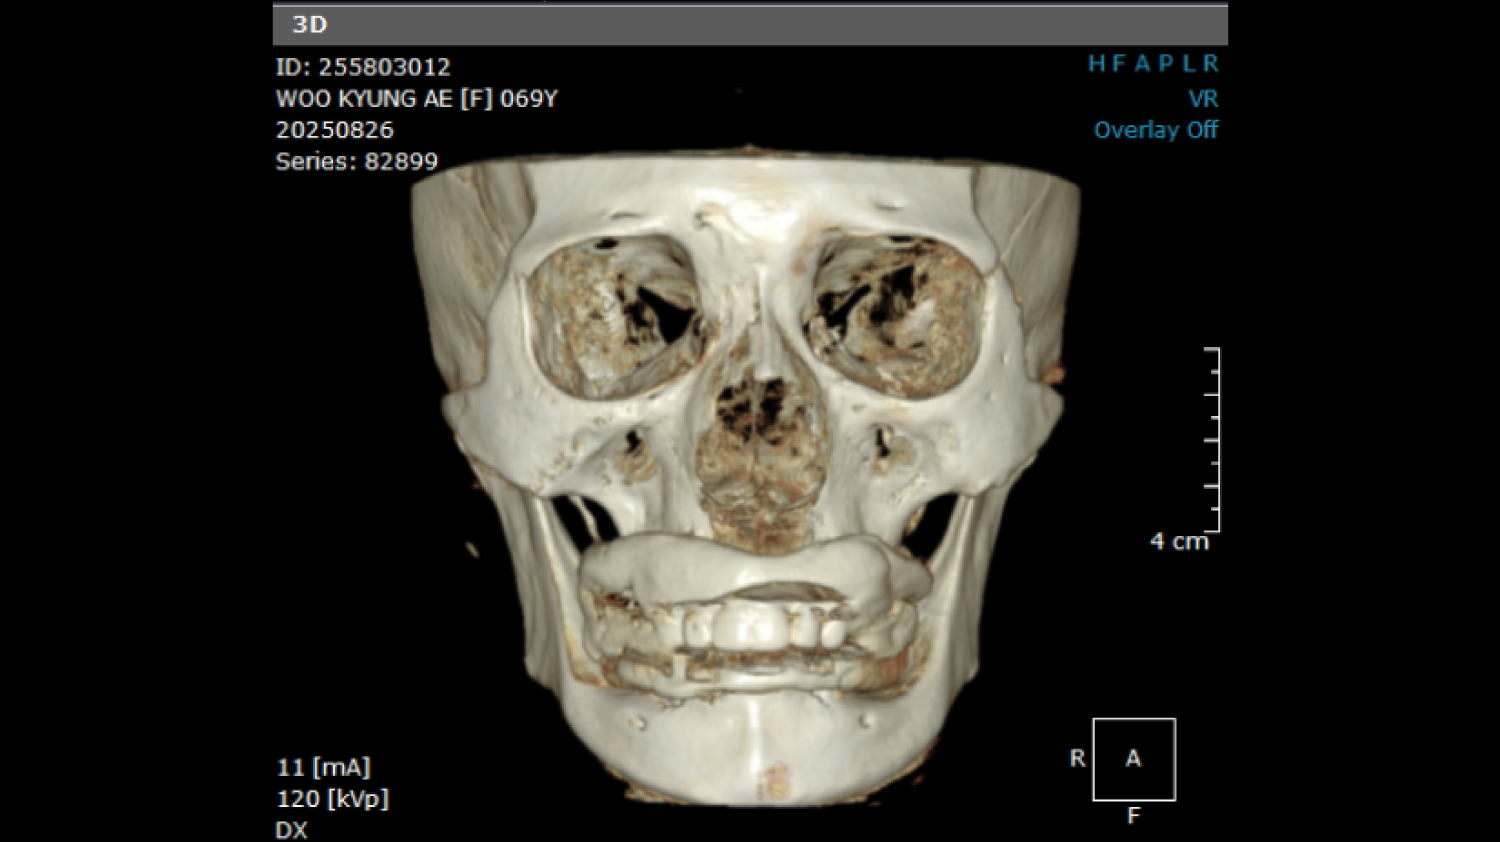

Course Overview

This course presents simplified yet clinically precise workflows for edentulous patients, enhancing both efficiency and patient comfort. Using the JB Tray, participants will learn how to combine custom tray fabrication, final impression, and jaw relation records in a single appointment, supported by digital processing and a live demonstration.

The program also introduces the JB Fork system, which integrates CBCT imaging and anterior reference points to enable one-step surgical stent fabrication without repeated impressions. Through practical demonstrations, attendees will see how this approach streamlines implant surgery while maintaining accuracy. The course concludes with insights into plasma surface treatment in implantology, highlighting its role in advancing clinical outcomes.

• One-Step Surgical Stent Fabrication Using JB Fork and CBCT.

Director’s Clinical Cases

Director’s Clinical Cases

One-Step Surgical Stent Fabrication with JB Fork

• Radiopaque JB Fork and the role of six anterior reference points: Registration with CBCT and integration with facial scanners

• One-step avatar creation without additional clinical procedures

• Surgical stent design and its application in implant surgery

• Live demonstration of JB Fork application in a patient case

Real patient application and taking CBCT, JB fork scanning(Prof Huh) |

Surgical stent design with all guides and implant studio software. (Prof Huh) |

One-Step Surgical Stent Fabrication with JB Fork

• Radiopaque JB Fork and the role of six anterior reference points: Registration with CBCT and integration with facial scanners

• One-step avatar creation without additional clinical procedures

• Surgical stent design and its application in implant surgery

• Live demonstration of JB Fork application in a patient case

Real patient application and taking CBCT, JB fork scanning(Prof Huh)

Surgical stent design with all guides and implant studio software. (Prof Huh)